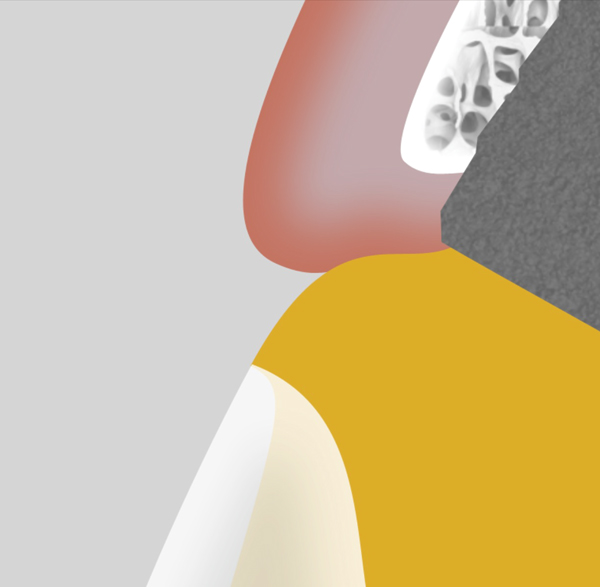

Fig 5. The “over-contoured” abutment design will displace the soft tissue apically. This design can be used strategically to reposition the peri-implant tissue to its desired position.

Figure 5

Fig 6. Useful in conjunction with immediate load scenarios, the “under-contoured” abutment design allows space for a potential increase in soft-tissue volume or a draping of tissue coronally. This design is created in the provisional restoration and left in position for at least 4 months.

Figure 6